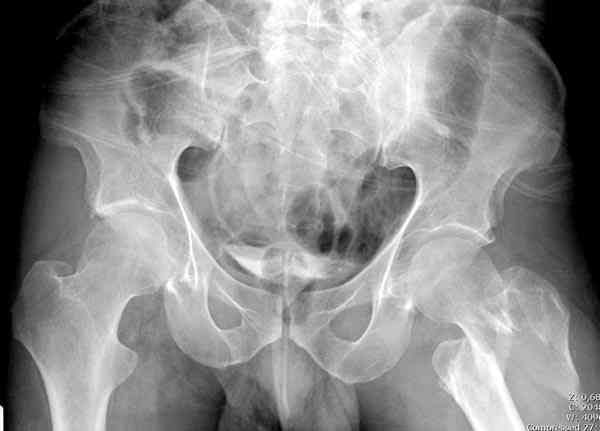

Применили проксимальную Synthes Locking plate, из-за множественных фрагментов посчитали более приемлемым в этом случае (клиника университетская, резиденты должны имет возможность созерцать разные варианты остеосинтеза).

Также старался минимизировать доступ на уровне перелома с субвастус доступом, диафиз фиксирован перкутанно, не стали гонятся за малым вертелом, как смог зафиксировал.

Перелом из четырех фрагментов, не стабильный (лекция Michael R. Baumgaertner, http://www.hwbf.org/ota/bfc/baumg/exp.htm), нужна стабильная фиксация.

Фиксация таких нестабильных чрезвертельных и reverse obliquity субтрохантерик переломов всегда была сложной задачей и ранее использовали Blade Plate. Но многие локальные общие ортопеды, к которым, в основном поступают такие больные, имели трудности с применением импланта, где необходимо было точная калькуляция по введению Blade и поэтому Synthes разработал Proximal Locking plate как альтернативу, где три проксимальные шурупа в разных направлениях создают концепцию угловой стабильности Blade Plate.